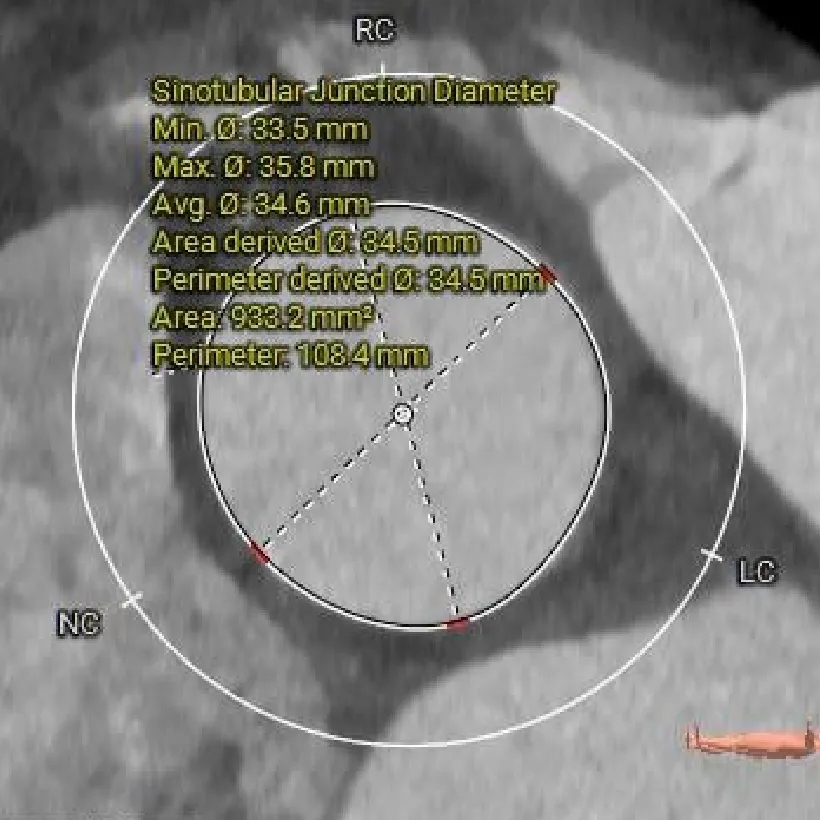

STJ:

34.5mm